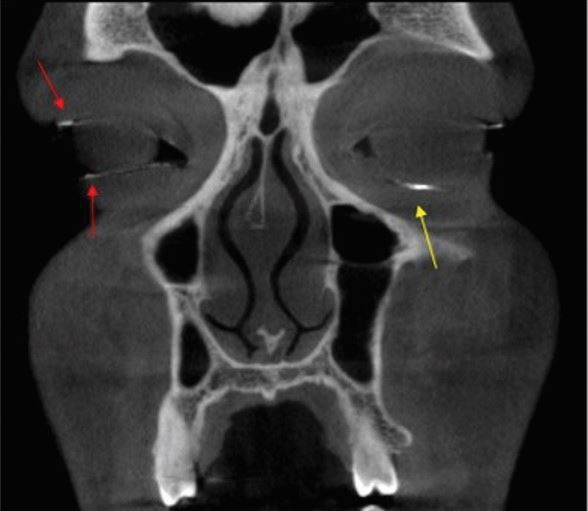

Fig. 1 | British Dental Journal